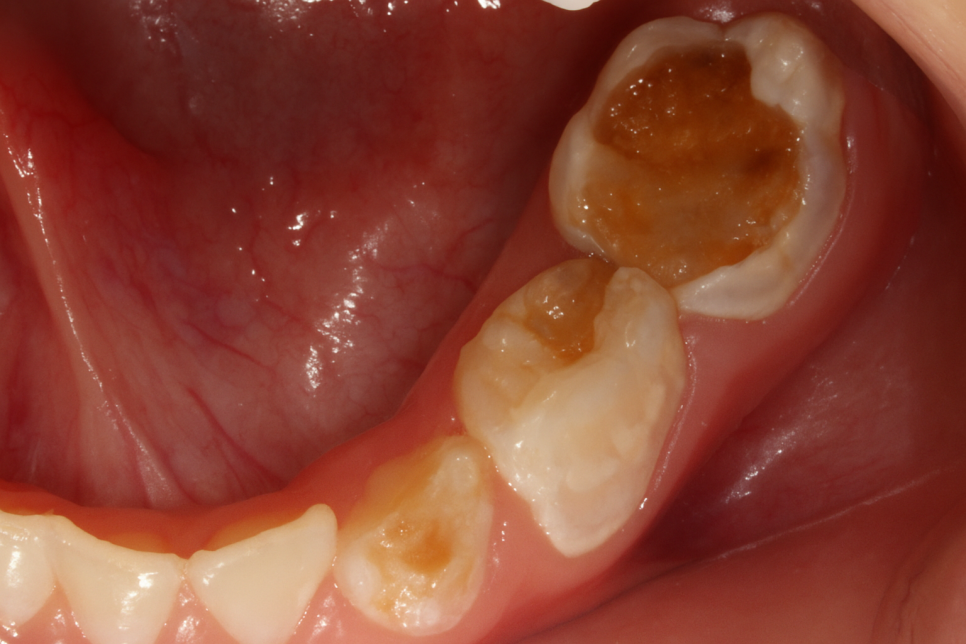

만약 이가 썩었거나 잇몸에 염증이 생겨났다 의심되면

추가로 방사선 사진을 찍어 면밀히 들여다봅니다.

만 12세를 기준으로 영구치에

충치가 생긴 적 있는 아이들이 몇 명인지

조사한 적이 있습니다.

OECD 국가는 평균 '1.2개'였는데,

한국은 평균적으로 '1.8개'라는

조사 결과가 나왔습니다.

평균보다 더 높은 비중을 차지하고 있죠.

그렇기에 어린이 충치를 예방할 수 있는 제도가 절실하죠.